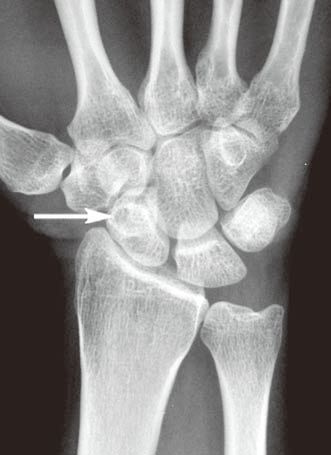

图1左腕手舟骨骨内腱鞘囊肿

A

B

C

D

左腕正位X线平片(A)示手舟骨远部骨内一小的透亮区。冠状位T1WI(B)示骨内病变呈低信号(箭)。冠状位(C)和横轴位(D)脂肪抑制T2WI示病变呈高信号,提示为液体(箭)